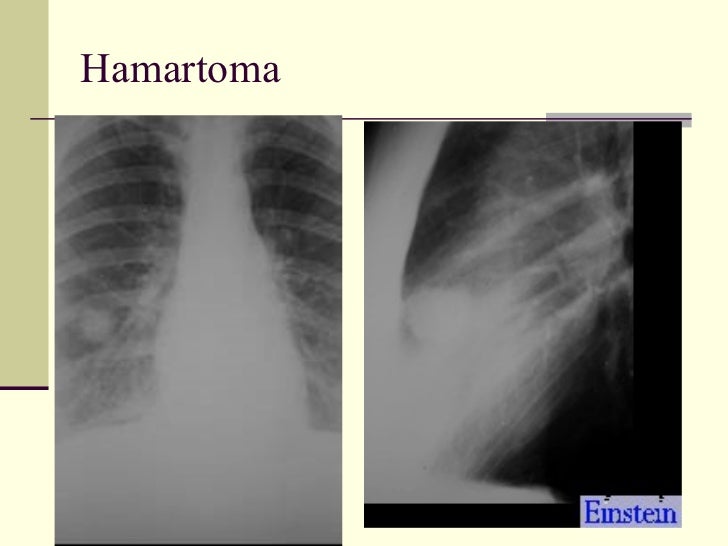

65. 73. <ul><li>Solitary Pulmonary Nodule </li></ul><ul><li>1. Bronchogenic ca </li></ul><ul><li>2. Hamartoma </li></ul><ul><li>3. Histoplasmoma </li></ul><ul><li>4. TB granuloma </li></ul><ul><li>5. Bronchial adenoma </li></ul><ul><li>6. Solitary met </li></ul><ul><li>7. Round pneumonia </li></ul><ul><li>8. Rounded atelectasis </li></ul>

66. 74. Hamartoma